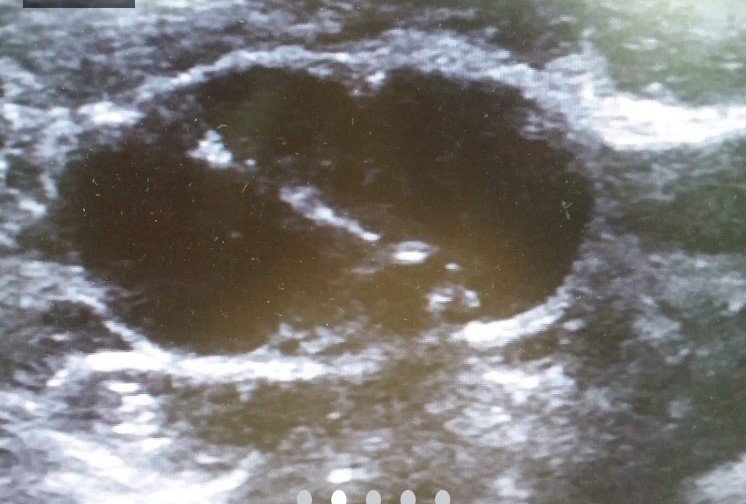

Kidney Interventions